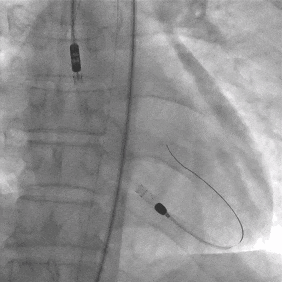

操作要点:DSA引导下穿刺左侧股动脉,置入配套可撕开导管鞘;导管跨主动脉弓及主动脉瓣,DSA实时定位后启动系统。

即时效果:SynFlow®3.0启动后左心衰症状显著缓解,心脏超声显示左心室缩小、血流瘀滞改善。

术后第1天:ECMO流量2.8L/min + SynFlow®3.0流量2.05L/min,维持窦性心律及血流动力学稳定。